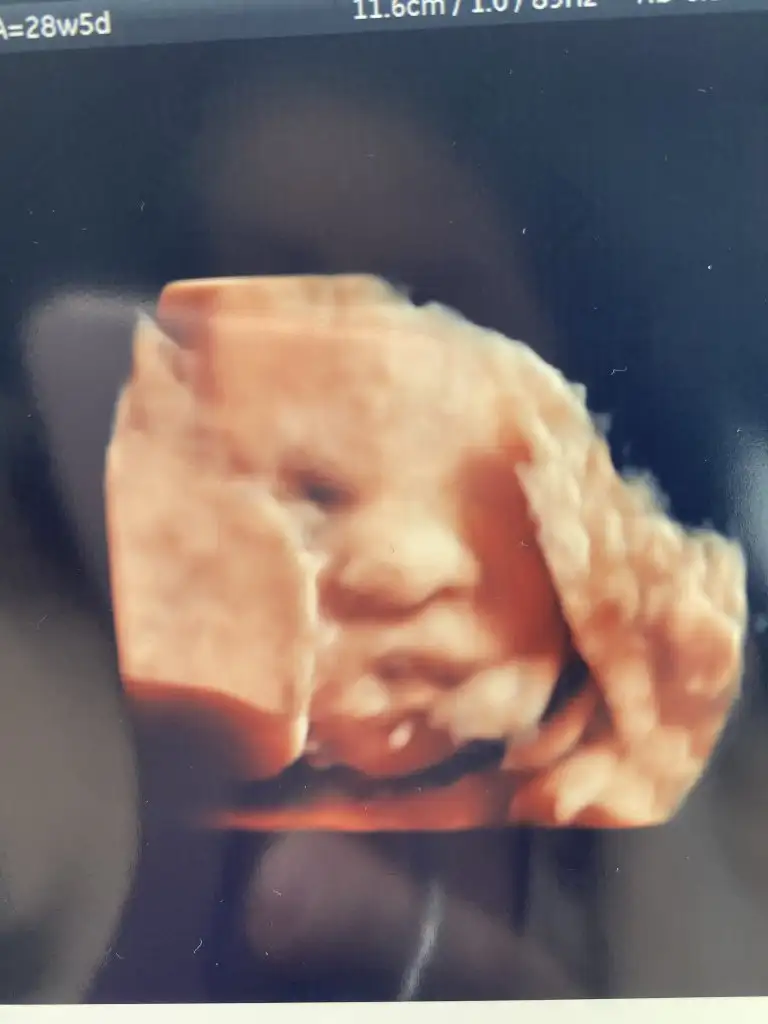

1230 gr37 cm olmuş güzel kızım

Herşey yolunda rahim ağzı kapalı serviks uzunlugu 43 dedi. Yüzünü plasentaya dayamış yine sağolsun pek net resim alamadık